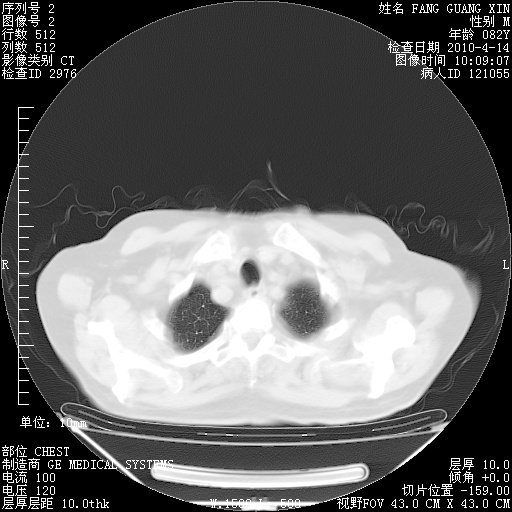

4月14日肺部CT

23.JPG

24.JPG

25.JPG

26.JPG